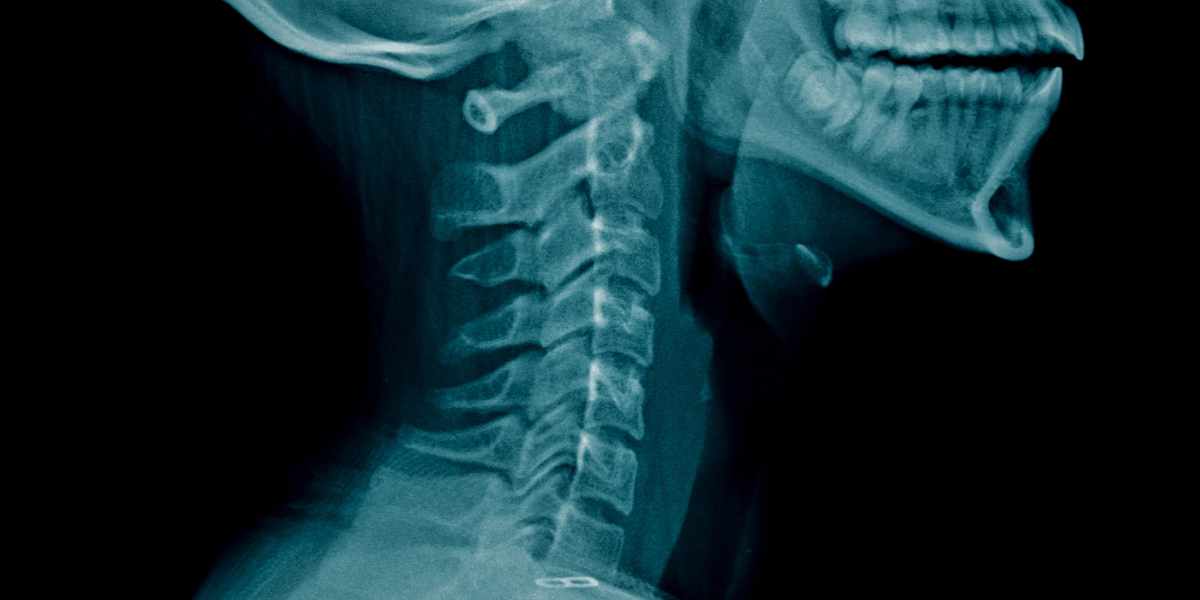

Cervical Spondylosis, also known as cervical osteoarthritis or neck arthritis, is a degenerative condition affecting the cervical spine (neck area). This condition typically develops over time due to wear-and-tear on the vertebrae and discs in the neck. Dr. Rajeshwari, based in Hyderabad, offers the best treatment for cervical spondylosis.

Imaging X-rays, MRI (Magnetic Resonance Imaging), or CT (Computed Tomography) scans to visualize structural changes in the cervical spine.